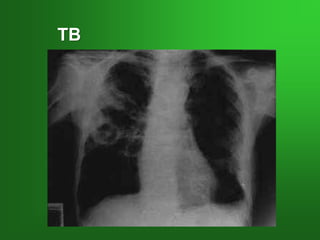

TB